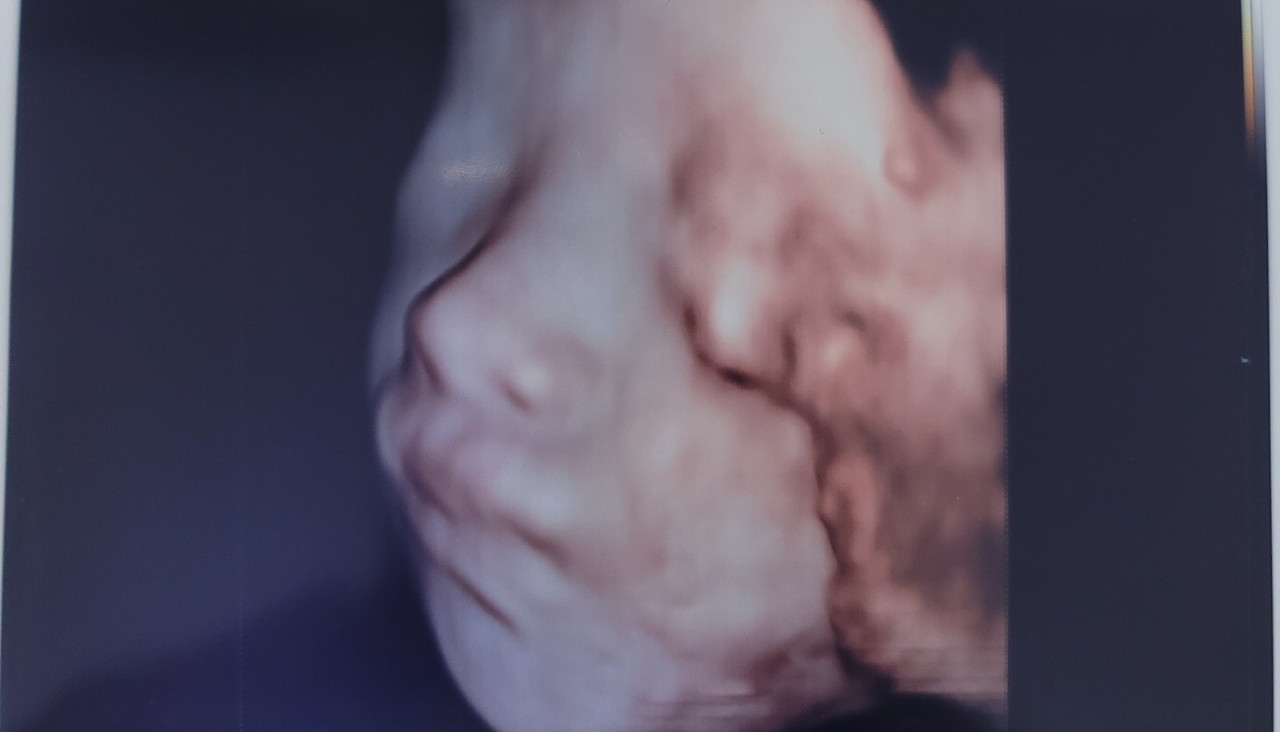

우리 까꿍이의 입초 사진이다.

몇 장 더 찍긴 했지만 이 두 장이 그나마 얼굴이 잘 보이는 사진이었다.

"하, 내 코 닮았어."

첫 번째 사진을 찍었을 때 보자마자 남편이 이렇게 얘기하며 안타까워했다.

"아냐, 이 사진 보면 내 코 닮은 거 같기도 한데..."

첫 번째 사진상에서는 남편의 코처럼 코가 낮고 코평수가 가로로 벌어져 있는 듯 보였는데

두 번째 사진 옆모습에서는 또 나름 콧대가 있는 거 같아 내 코처럼 보이기도 했다.